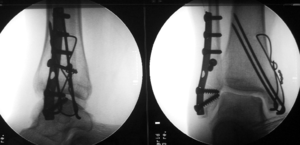

Treatment of ankle fractures is dictated by the stability of the ankle joint. Certain fractures patterns are deemed stable, and may be treated similar to ankle sprains. All other types require surgery, most often an open reduction and internal fixation (ORIF), which is usually performed with permanently implanted metal hardware that holds the bones in place while the natural healing process occurs. A cast or splint will be required to immobilize the ankle following surgery.